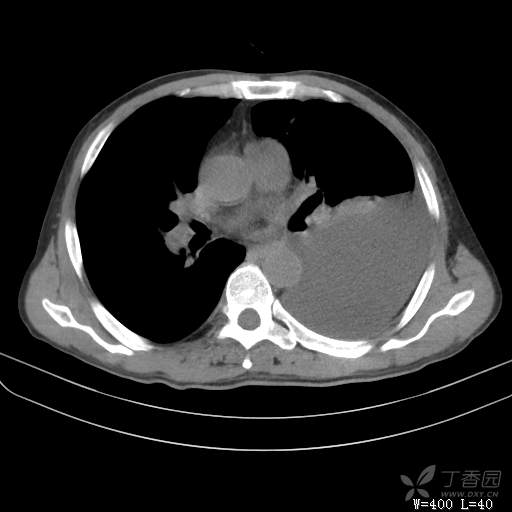

简要病史:胸闷、憋气伴低热1月

辅助检查:白细胞数目4.41 × 10^9/L,中性粒细胞百分比82.1%,*血红蛋白111g/L,*血小板数目91 × 10^9/L,凝血四项:凝血酶原时间12.5秒,国际标准化比值1.07,活化部分凝血酶原时间36.1秒,纤维蛋白原浓度6.52g/L,肾功能示:肌酐47.4umol/L,尿酸150umol/L,电解质示:钠133.5mmol/L,D-二聚体0.88mg/L,血沉67.71MM/H,C-反应蛋白114.6mg/L,肝功能:*总蛋白49.6g/L,*白蛋白27.4g/L,查胸水常规及胸水生化提示渗出液,胸水ADA154U/L,查胸水病理未见肿瘤细胞。超声:腹膜后有3~4枚肿大淋巴结,直径1~1.5厘米,余浅表淋巴结不大。

临床诊断:左侧胸腔积液

治疗经过:胸水引流。胸水白蛋白23.8克/升,乳酸脱氢酶275单位/升,胸苷激酶182单位/升,胸水外观黄色混浊,总细胞4320个/微升,白细胞4320个/微升,单核细胞80%,多核细胞20%。考虑结核性胸膜炎,结果查肿瘤标志物、胸水细胞学阴性,胸水TB—DNA阴性,结核菌素试验+,结核抗体阴性,TB-SPOT阴性,胸膜活检阴性。怎么办?

大家猜猜胸水原因是什么?